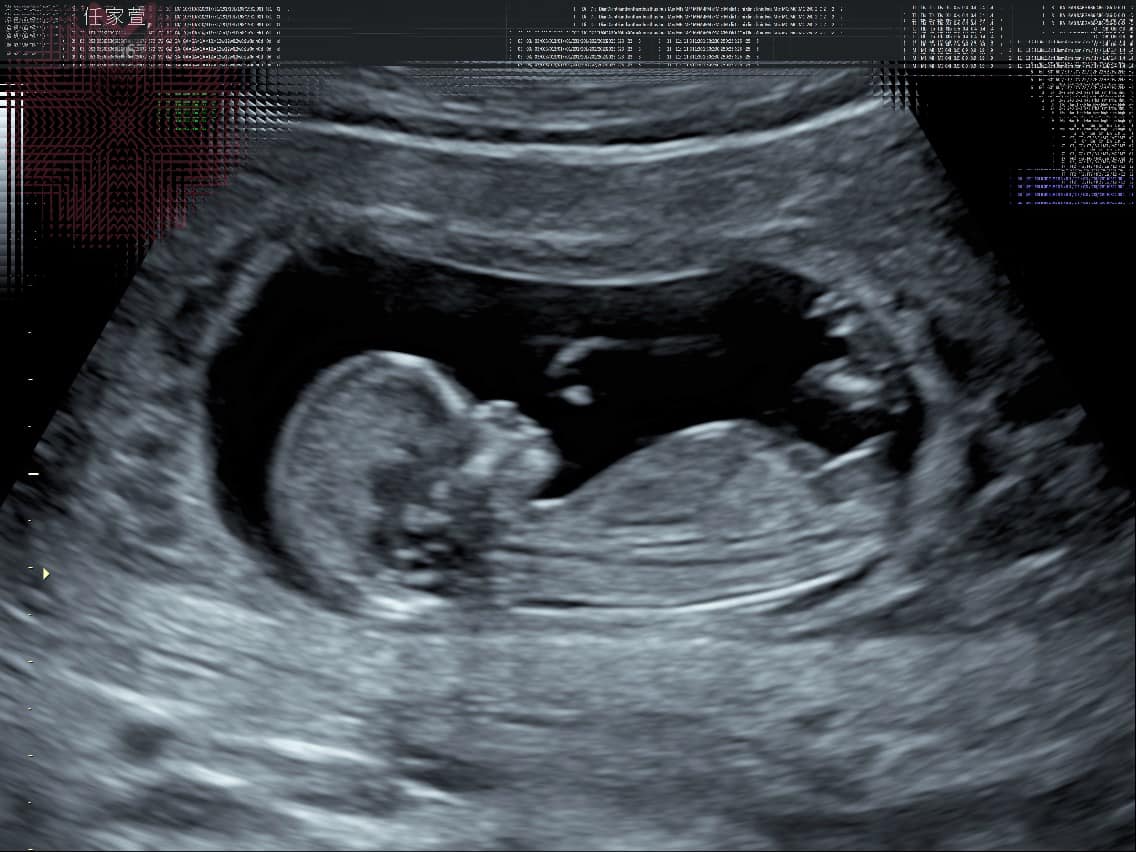

任家萱(Selina)去年3月认爱小7岁的圈外男友小徐,两人一直很幸福甜蜜,她今日毫无预警的在电台宣布自己怀孕的消息,宝宝目前12周左右。

Selina透露小宝宝小名叫“小腰果”,因为去年去越南时印象最深刻的就是腰果,而且在去越南时自己应该已经怀孕了,她觉得这应该是一个缘分吧,所以就想要取名小腰果,因为现在还不知道性别。